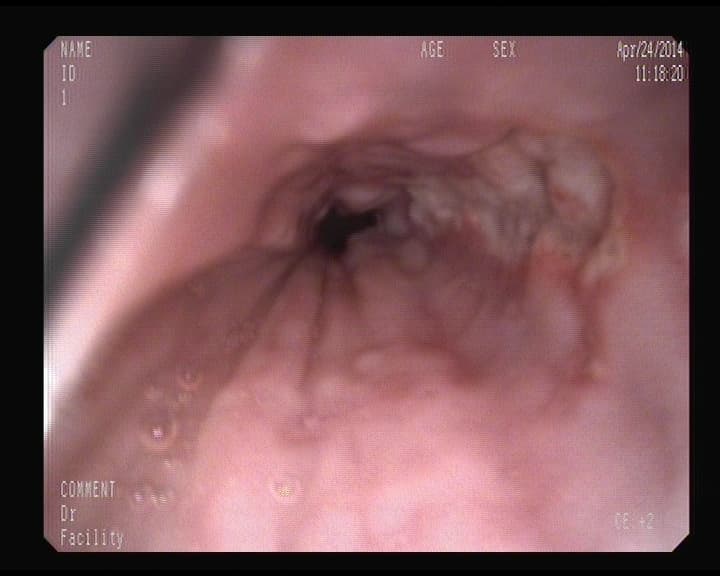

Esofagitis Eosinófilica

El Esófago está infiltrado por células eosinófilas, produciendo resequedad del tejido, y gran aumento de la presión interior, provocando en la persona episodios de atragantamientos- Disfagia transitorias- Síntoma agobiante, atoramiento. Desaparece en minutos, u horas, tranquilizarse, no ingerir nada, y esperar. Si queda el alimento impactado Acudir a un centro hospitalario. No se considera proceso de tipo inmunológico.